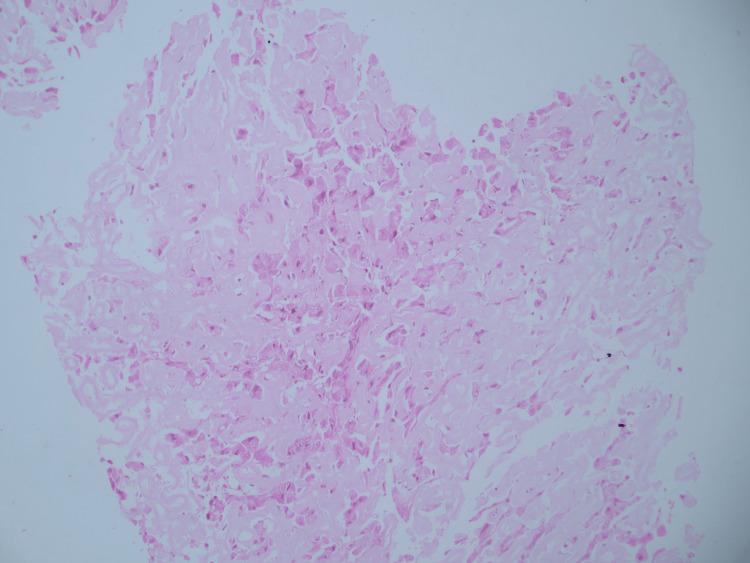

Amyloidosis is a rare infiltrative multisystemic disorder characterized by protein misfolding, leading to progressive organ failure. It can be either acquired or hereditary. Very few case reports regarding hepatic amyloidosis with Budd-Chiari syndrome have been reported up to date. We report the case of a 45-year-old man presenting with abdominal distension, pain in the abdomen, and jaundice. Through right hepatic vein cannulation, HVPG (hepatic venous pressure gradient) was found to be 10 mmHg. The liver biopsy revealed near-total replacement of hepatic parenchyma by amorphous congophilic deposits with obliteration of sinusoids. Hepatic amyloidosis with hepatic venous occlusion is a rare entity.

淀粉样变性是一种罕见的浸润性多系统疾病,其特征为蛋白质错误折叠,可导致进行性器官衰竭。它可分为获得性或遗传性。迄今为止,关于肝淀粉样变性合并布加综合征的病例报告极少。我们报告一例45岁男性患者,表现为腹胀、腹痛和黄疸。通过右肝静脉插管发现肝静脉压力梯度(HVPG)为10 mmHg。肝脏活检显示肝实质几乎完全被无定形嗜刚果红沉积物替代,肝血窦闭塞。肝淀粉样变性合并肝静脉闭塞是一种罕见的病症。